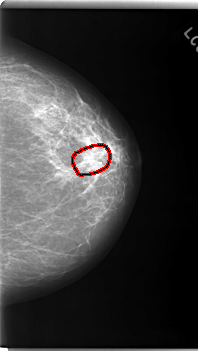

C_0170_1.LEFT_MLO

FILE: C_0170_1.LEFT_MLO.OVERLAY

TOTAL_ABNORMALITIES 1

ABNORMALITY 1

LESION_TYPE MASS SHAPE OVAL MARGINS SPICULATED

ASSESSMENT 5

SUBTLETY 4

PATHOLOGY MALIGNANT

TOTAL_OUTLINES 1

BOUNDARY